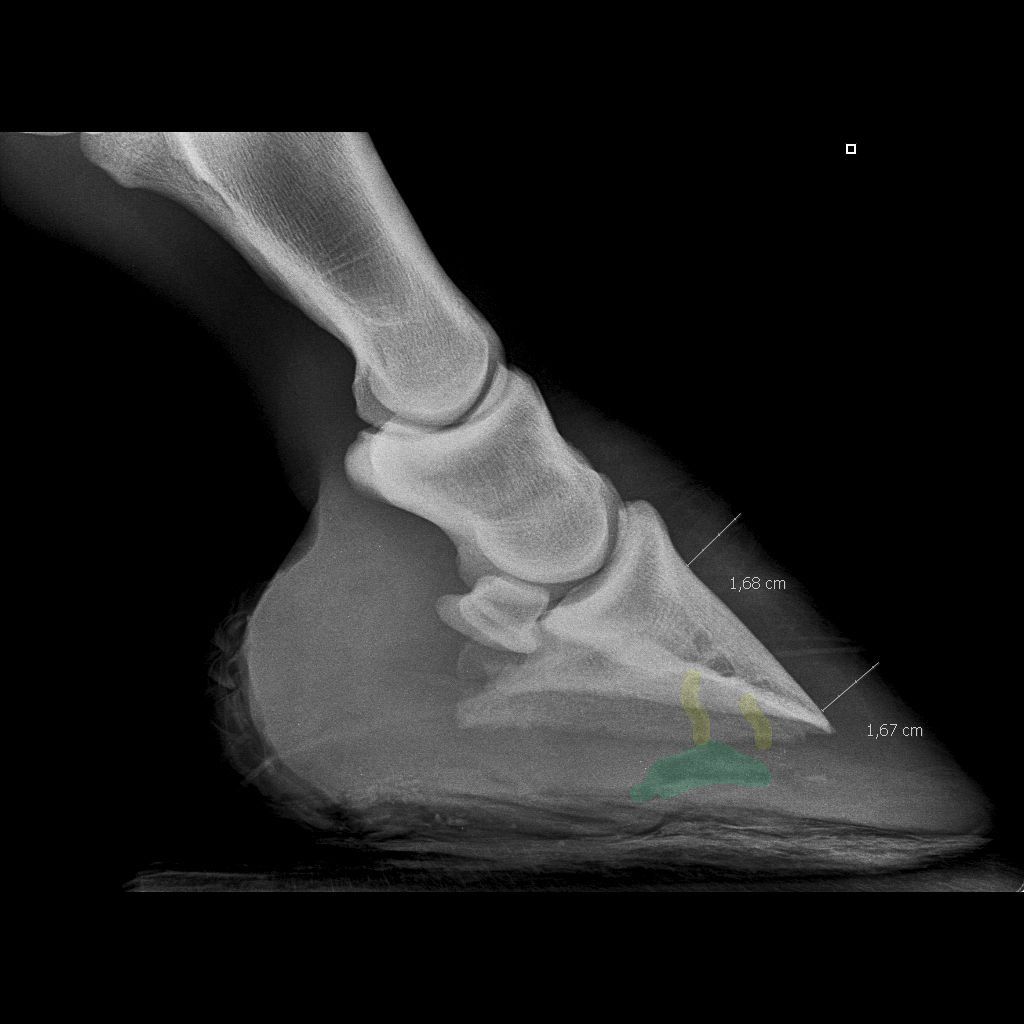

| Dire merci | ![]() Les fistules dont je parle sont en jaune, le vert c'est je pense le trou creusé. Après je ne fait que des hypothèses d'amateur évidement ![]() |

| Dire merci | la finadine c'est un anti-inflammatoire, tiens c'est bon à savoir car ma collègue m'en parlait comme d'un produit miracle... oziris, ah oui, avec ton dessin, je vais mieux comprendre : donc le vert moi je pensais que c'était l'abcès parceque si c'est le trou qu'il a creusé vachement profond ![]() laure brr, moi non plus je ne comprend pas trop pourquoi referrer c'est un peu risqué je trouve, mais je pense qu'il pensait que ca soulagerait la jument au niveau des appuis; mais moi ca m'ennerve car du coup, je dois arrêter les pansements, alors le crottin et tout vont se loger dans le trou bien comme il faut....ca ne me dit rien qui vaille.... je dois faire bain de javel tous les jours + goudron, j'ai peur que ca bouche le tout moi... ![]() Enfin bon, c'est pas moi le véto alors je me tais et j'execute.... val : non, il vient de Nantes celui-là. une question : c'est quand il y a inflammation qu'il y a douleur ou c'est indépendant ? Un anti-inflammatoire est un anti-douleur parecqu'en réduisant l'inflammation ont réduit la douleur ou c'est autre chose ? Vous pouvez m'expliquer ? Message édité le 30/01/10 à 19:26 |